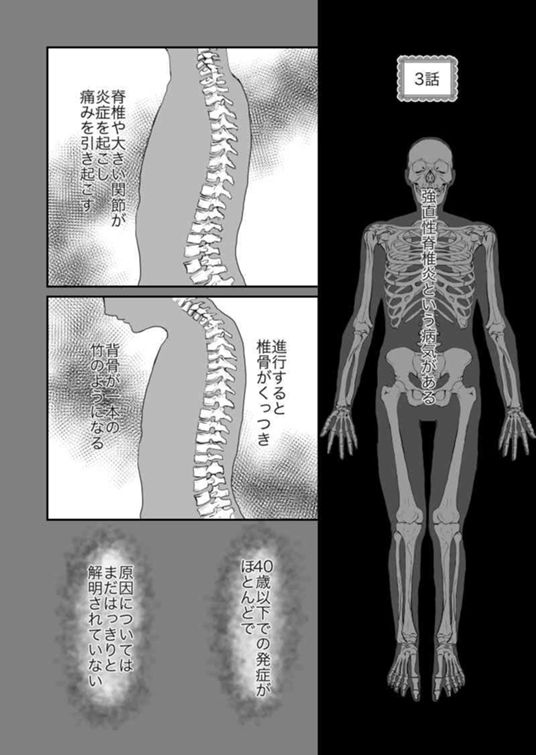

3話 難病持ちの妊婦